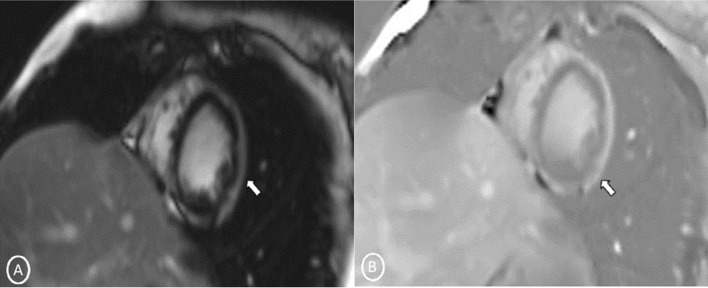

A 19-year-old female had presented to our Emergency Department, complaining of sudden severe chest and epigastric pain since 1 day, which was associated with sweating. The pain was radiating to neck and left arm. The pain did not relieve on rest but subsided on medications. Similar episodes were also reported in the past few days, however, with less severity. The patient confirmed to not having shortness of breath, palpitation, syncope, dizziness, nausea, emesis, fever, or cough. There was no history of any previous cardiac ailment/surgery/other identifiable cardiovascular risk factors or any other history of infection. There is no evidence to suggest chest wall trauma. There is no history of comorbidities or any history of smoking. There is no significant family history or any similar past history. Upon admission, patient was conscious, alert with heart rate of 86 bpm, blood pressure measuring 110/60 mm Hg, 97% oxygen saturation at room air, temperature of 36.4 °C, and respiration rate of 15 breaths/min. The cardiac biomarker troponin T levels were extremely raised, measuring 50,000 pg/ml, and CK-MB was raised, measuring 111U/Lt. Laboratory findings showed that inflammation markers were normal, C-reactive protein (5.8.0 mg/L) and D-dimer (94 ng/mL). Other laboratory findings such as lipid profile, complete blood count, electrolytes, fasting blood glucose, HBA1c, and renal and liver function tests were normal. Cardiac auscultation showed normal S1, S2 without murmurs or pericardial rub and any sign of heart failure. Initial ECG revealed ST segment elevation in the leads I, aVL, V4, V5, and V6 leads, normal sinus rhythm (60 beats per min) without any other abnormalities (Fig. 1), which was resolved by day 3. Arrhythmias were not found during continuous cardiac monitoring. Echocardiogram showcased an ejection fraction of the left ventricle to be 60%, whereas the echocardiographic metrics were not very significant. Patient was then treated as ACS with a salicylate-based nonsteroidal anti-inflammatory drug (NSAID), anticoagulants, and anti-thrombolytics. CMR was done on 3 T MRI machine with acquisition including T2/STIR Dark blood four-chamber long axis; CINE images in short axis, long axis, RVOT, and LVOT; and early dynamic gadolinium enhancement images and delayed gadolinium enhancement in PSIR images. T2/STIR Dark blood sequences showed T2 hyperintensity in the subepicardial region along left lateral wall (Fig. 2A, B). There was associated mild global hypokinesia with mildly reduced ejection fraction/systolic function (Fig. 3A, B). Patchy delayed gadolinium enhancement of intramural, subepicardial as all tans-mural enhancement with non-involvement of the subendocardium (suggesting a non-ischemic pattern) in multiple segments of cardiac basal (Fig. 4A, B), mid cavity (Fig. 5A, B), and apical cavity—with predominant involvement of lateral (Fig. 6A, B) and inferior wall segments in the basal cavity. There were no signs of infarction of myocardium; therefore, the patient was diagnosed with acute myocarditis (based on Lake Louise Criteria for Acute Myocarditis). Further, viral and autoimmune workups results were found to be negative. It included hepatitis (B, C), human immunodeficiency virus, Coxsackie virus, COVID-19, cytomegalovirus, Epstein–Barr virus (EBV), and Parvovirus B-19. On further analysis and detailed relevant history workup, the patient admitted to using cannabis for the past 1 year with last exposure being 3 days before admission. On the basis of detailed clinical history, findings on CMR with other negative viral markers, and possible etiological factors, a final diagnosis of myocarditis presumed secondary to marijuana/cannabis toxin abuse was made. Patient was released from the hospital on the seventh day with advised conservative treatment. The patient was counseled to abstain completely from cannabis or related drugs. Patient was advised to repeat a CMR control, three months later. A 3–4-month restriction on high-intensity activity was also given to the patient following discharge.